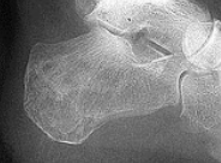

| What disease is this? | Sever's disease |